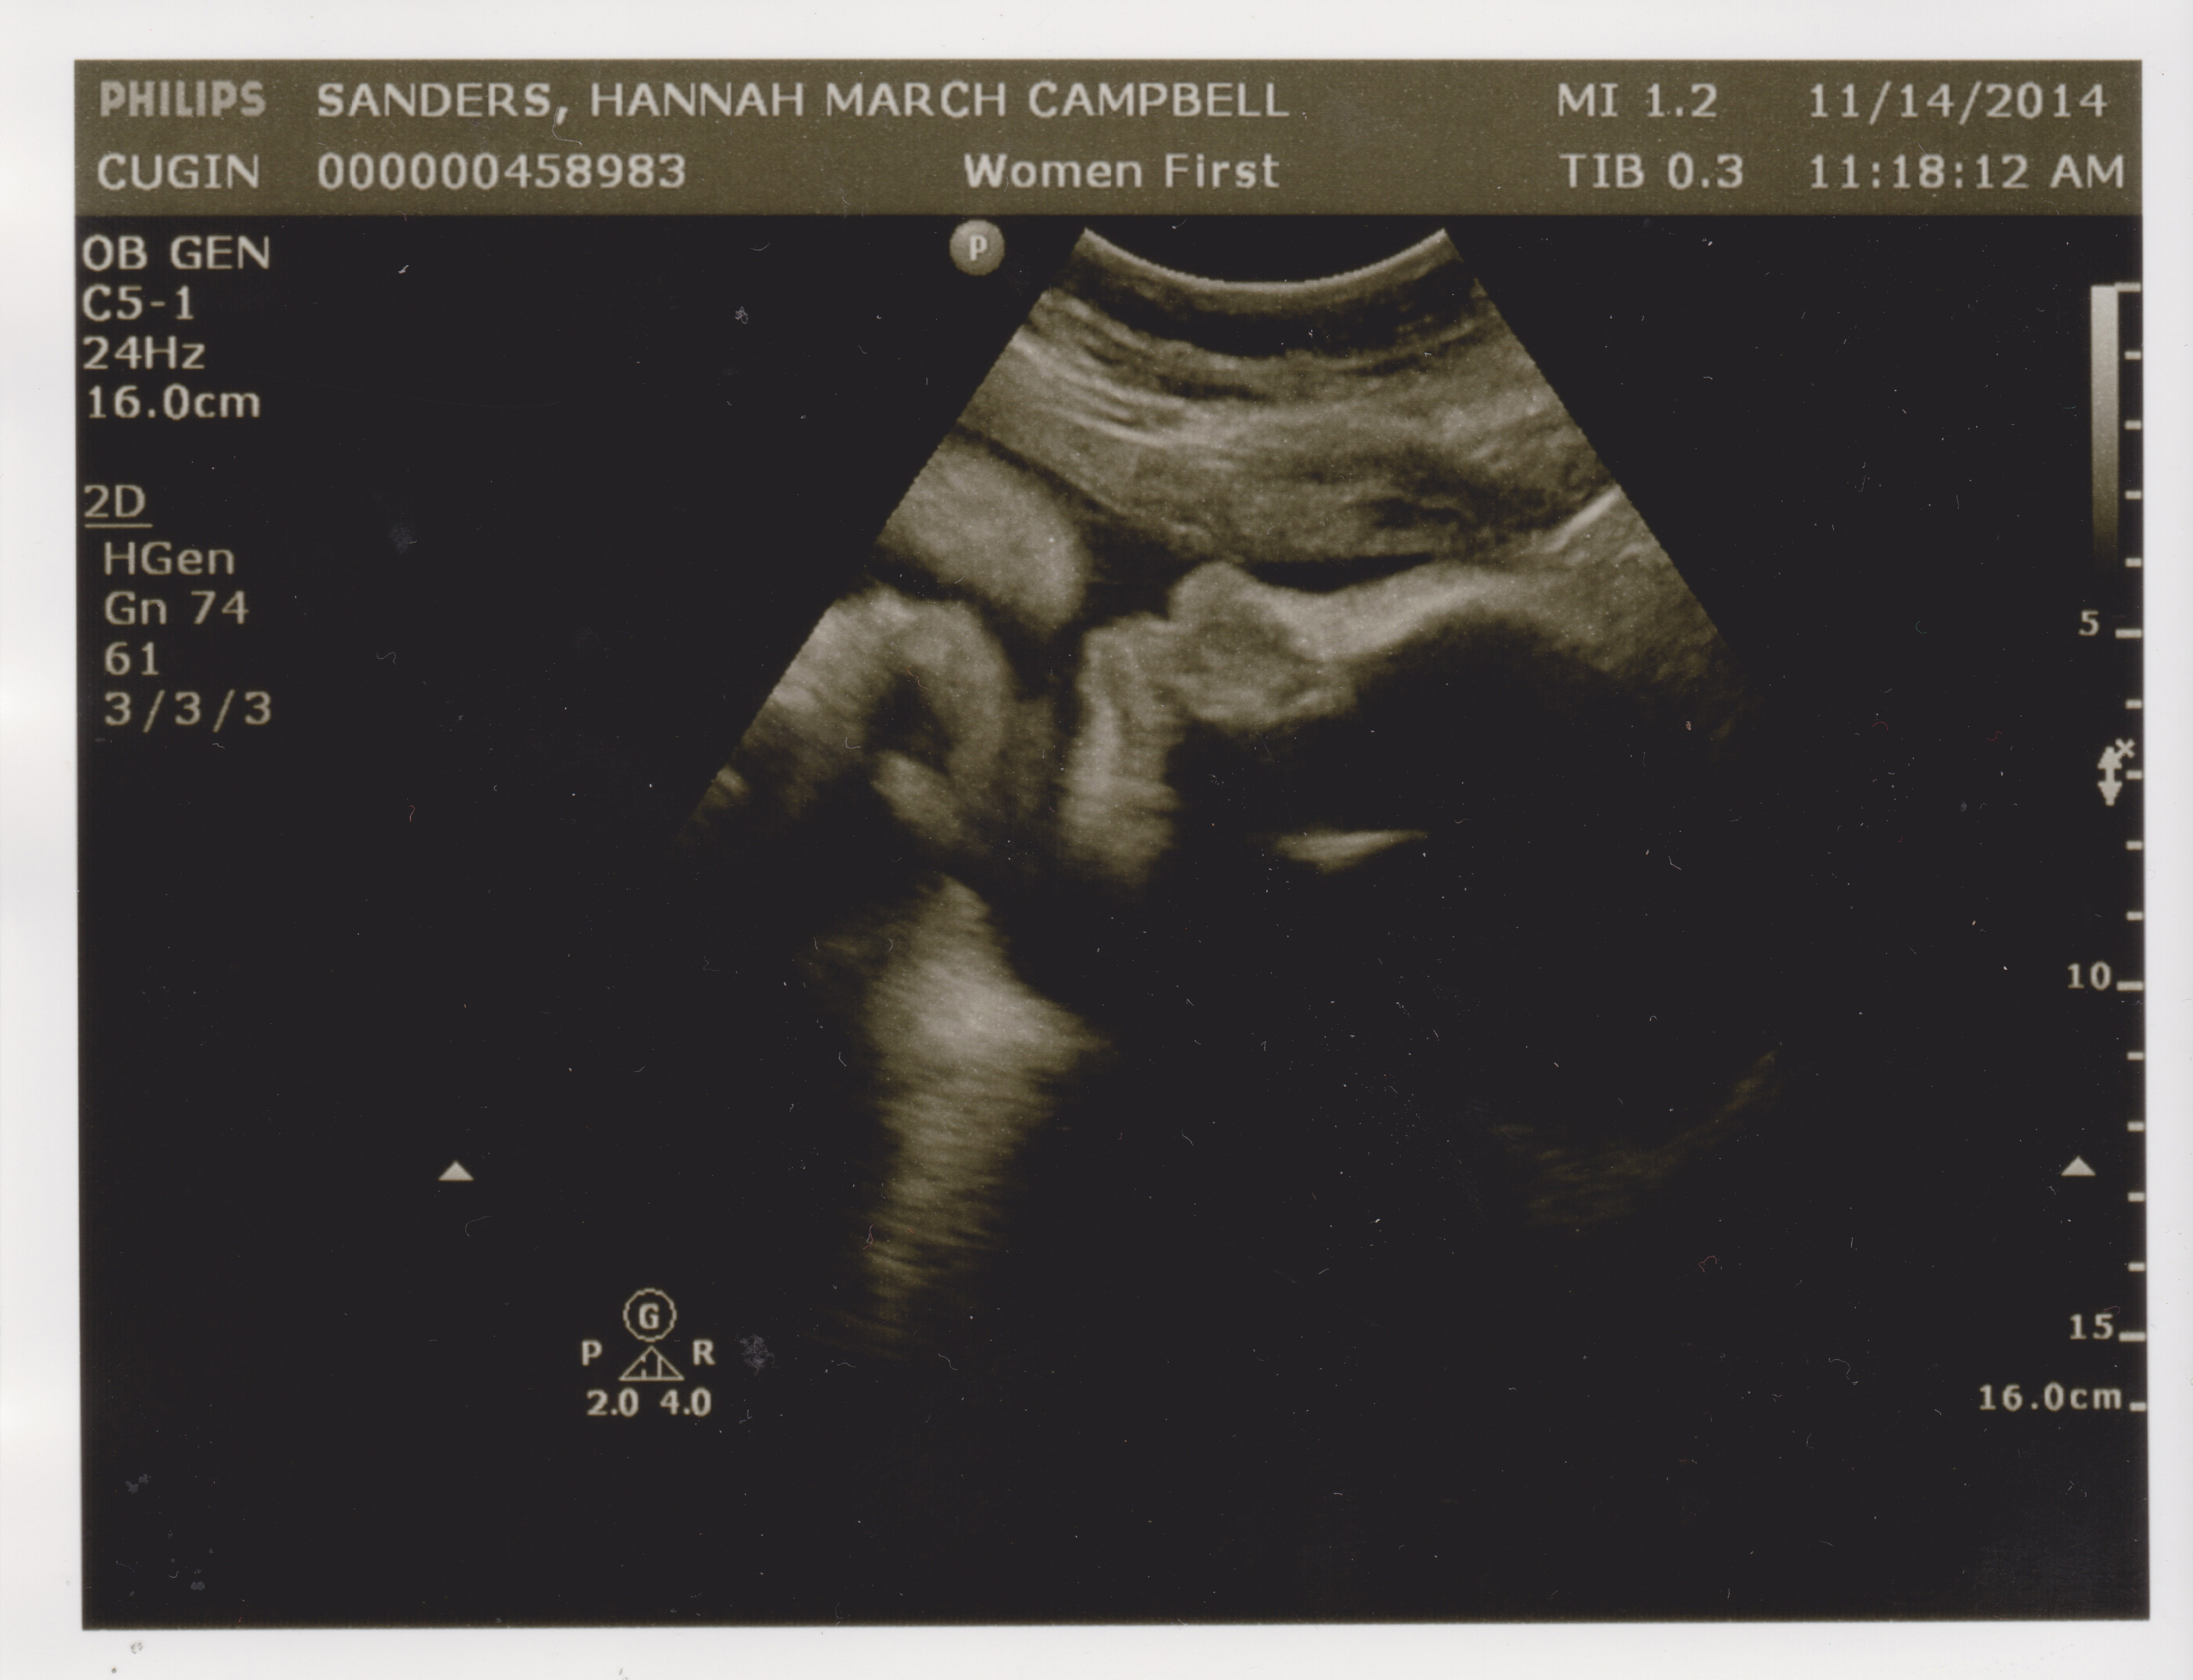

Another Friday, another doctor’s appointment. Today was Hannah’s second ultrasound in as many weeks, to check on the growth rate of the undersized nugget. In the last two weeks it’s gained a little less than half a pound, from 4lb. 5oz. to 4lb. 12oz. That was about a half pound less than the ultrasound tech. was hoping for, but Dr. Cugini doesn’t seem super concerned.

However, the baby is now under the 10th percentile for growth, so in order to prove everything’s OK, a new regimen begins. From here on in it’ll be two visits a week. Once a week we’ll go in for a BPP, an ultrasound that checks for growth and muscle-tone. Later in the week it’s another NST, the dreaded Non-Stress Test, where Hannah has air hockey paddles strapped to her belly for half an hour while the baby’s heartbeat blares like feedback at a death metal concert. Non-Stress indeed!